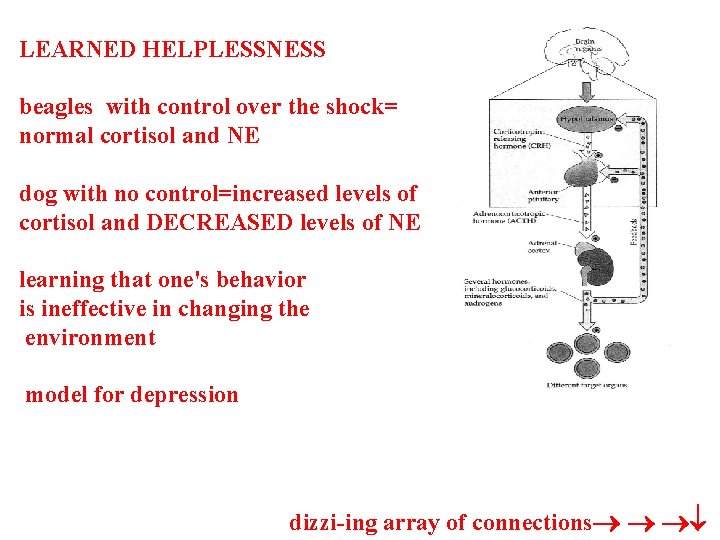

LEARNED HELPLESSNESS beagles with control over the shock= normal cortisol and NE dog with no control=increased levels of cortisol and DECREASED levels of NE learning that one's behavior is ineffective in changing the environment model for depression dizzi-ing array of connections